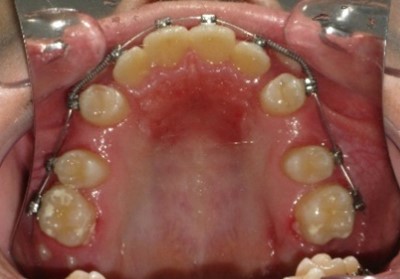

В полости рта: смыкание первых моляров по дистальному типу. Сужение зубных рядов в боковых отделах. 13 и 23 - вестибулярное и супраположение с дефицитом места в зубном ряду на величину ширины коронки клыка. Глубокая резцовая окклюзия.(рис.2.)

Рис.2.Смыкание зубных рядов пациента А. до лечения и окклюзионный вид.